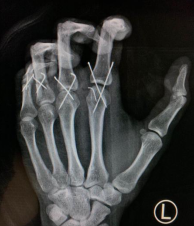

黎医生手术团队为李伟紧急进行了“左手2-5指清创再植术”。术中先清创,予克氏针固定骨折断端及关节,修复肌腱韧带断端,高倍显微镜下吻合左手2-5指血管神经,术中松止血带,血管通血良好。手术顺利,全程6小时。

术后即刻

术后